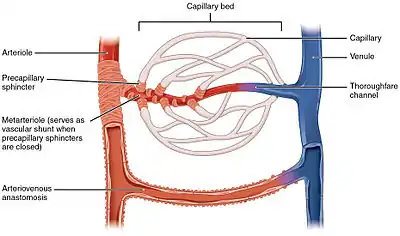

The microcirculation is the circulation of the blood in the smallest blood vessels, the microvessels of the microvasculature present within organ tissues.[1] The microvessels include terminal arterioles, metarterioles, capillaries, and venules. Arterioles carry oxygenated blood to the capillaries, and blood flows out of the capillaries through venules into veins.

Microvessels

The vessels on the arterial side of the microcirculation are called the arterioles, which are well innervated, are surrounded by smooth muscle cells, and are 10-50 μm in diameter.[2] Arterioles carry the blood to the capillaries, which are not innervated, have no smooth muscle, and are about 5-8 μm in diameter. Blood flows out of the capillaries into the venules, which have little smooth muscle and are 10-200 μm. The blood flows from the venules into the veins. Metarterioles connect arterioles and capillaries. A tributary to the venules is known as a thoroughfare channel.

The microcirculation has three major components: pre-capillary, capillary, and post-capillary. In the pre-capillary sector, arterioles, and precapillary sphincters participate. Their function is to regulate blood flow before it enters the capillaries and venules by the contraction and relaxation of the smooth muscle found on their walls. The second sector is the capillary sector, which is represented by the capillaries, where substance and gas exchange between blood and interstitial fluid takes place. Finally, the post-capillary sector is represented by the post-capillary venules, which are formed by a layer of endothelial cells that allow free movement of some substances.[3]